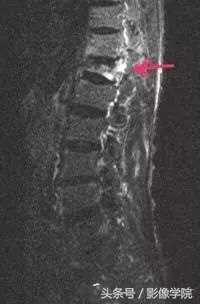

(2)MRI:可更准确地评估有无椎管压迫及骨折的新鲜程度,也是目前比较主要的检查。椎体内新鲜骨折所致的水肿表现为T2像和短T1反转恢复(STIR)序列信号增强及T1像信号减弱。一定要拍脂肪抑制像,以鉴别是否为新鲜骨折、肿瘤或是椎体内脂肪岛。

病例演示:老年女性患者,轻微外伤后出现胸背部疼痛不适

MRI提示胸12椎体新鲜骨质疏松性压缩骨折,诊断明确后局部麻醉下行经皮椎体后凸成形术(PKP)